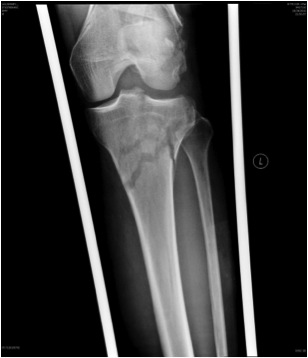

Knee

Byon et al. Injury 2018

- 87 knee ligament injuries in 429 femoral shaft fractures (20%)

- 20 PCL, 11 ACL, 16 MCL, 8 LCL and 32 multiligament knee injuries

- always assess knee after femoral stabilisation